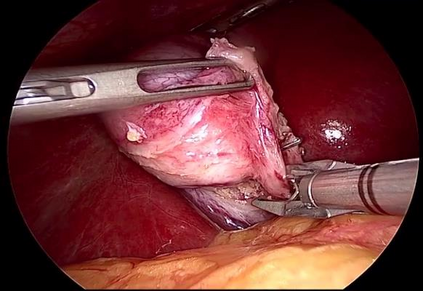

In addition to generating data and annotations, devising sensible data splitting strategies and evaluation metrics is essential for the creation of a benchmark dataset. This practice ensures consensus on the usage of the data, homogeneous assessment, and uniform comparison of research methods on the dataset. This study focuses on CholecT50, which is a 50 video surgical dataset that formalizes surgical activities as triplets of <instrument, verb, target>. In this paper, we introduce the standard splits for the CholecT50 and CholecT45 datasets and show how they compare with existing use of the dataset. CholecT45 is the first public release of 45 videos of CholecT50 dataset. We also develop a metrics library, ivtmetrics, for model evaluation on surgical triplets. Furthermore, we conduct a benchmark study by reproducing baseline methods in the most predominantly used deep learning frameworks (PyTorch and TensorFlow) to evaluate them using the proposed data splits and metrics and release them publicly to support future research. The proposed data splits and evaluation metrics will enable global tracking of research progress on the dataset and facilitate optimal model selection for further deployment.